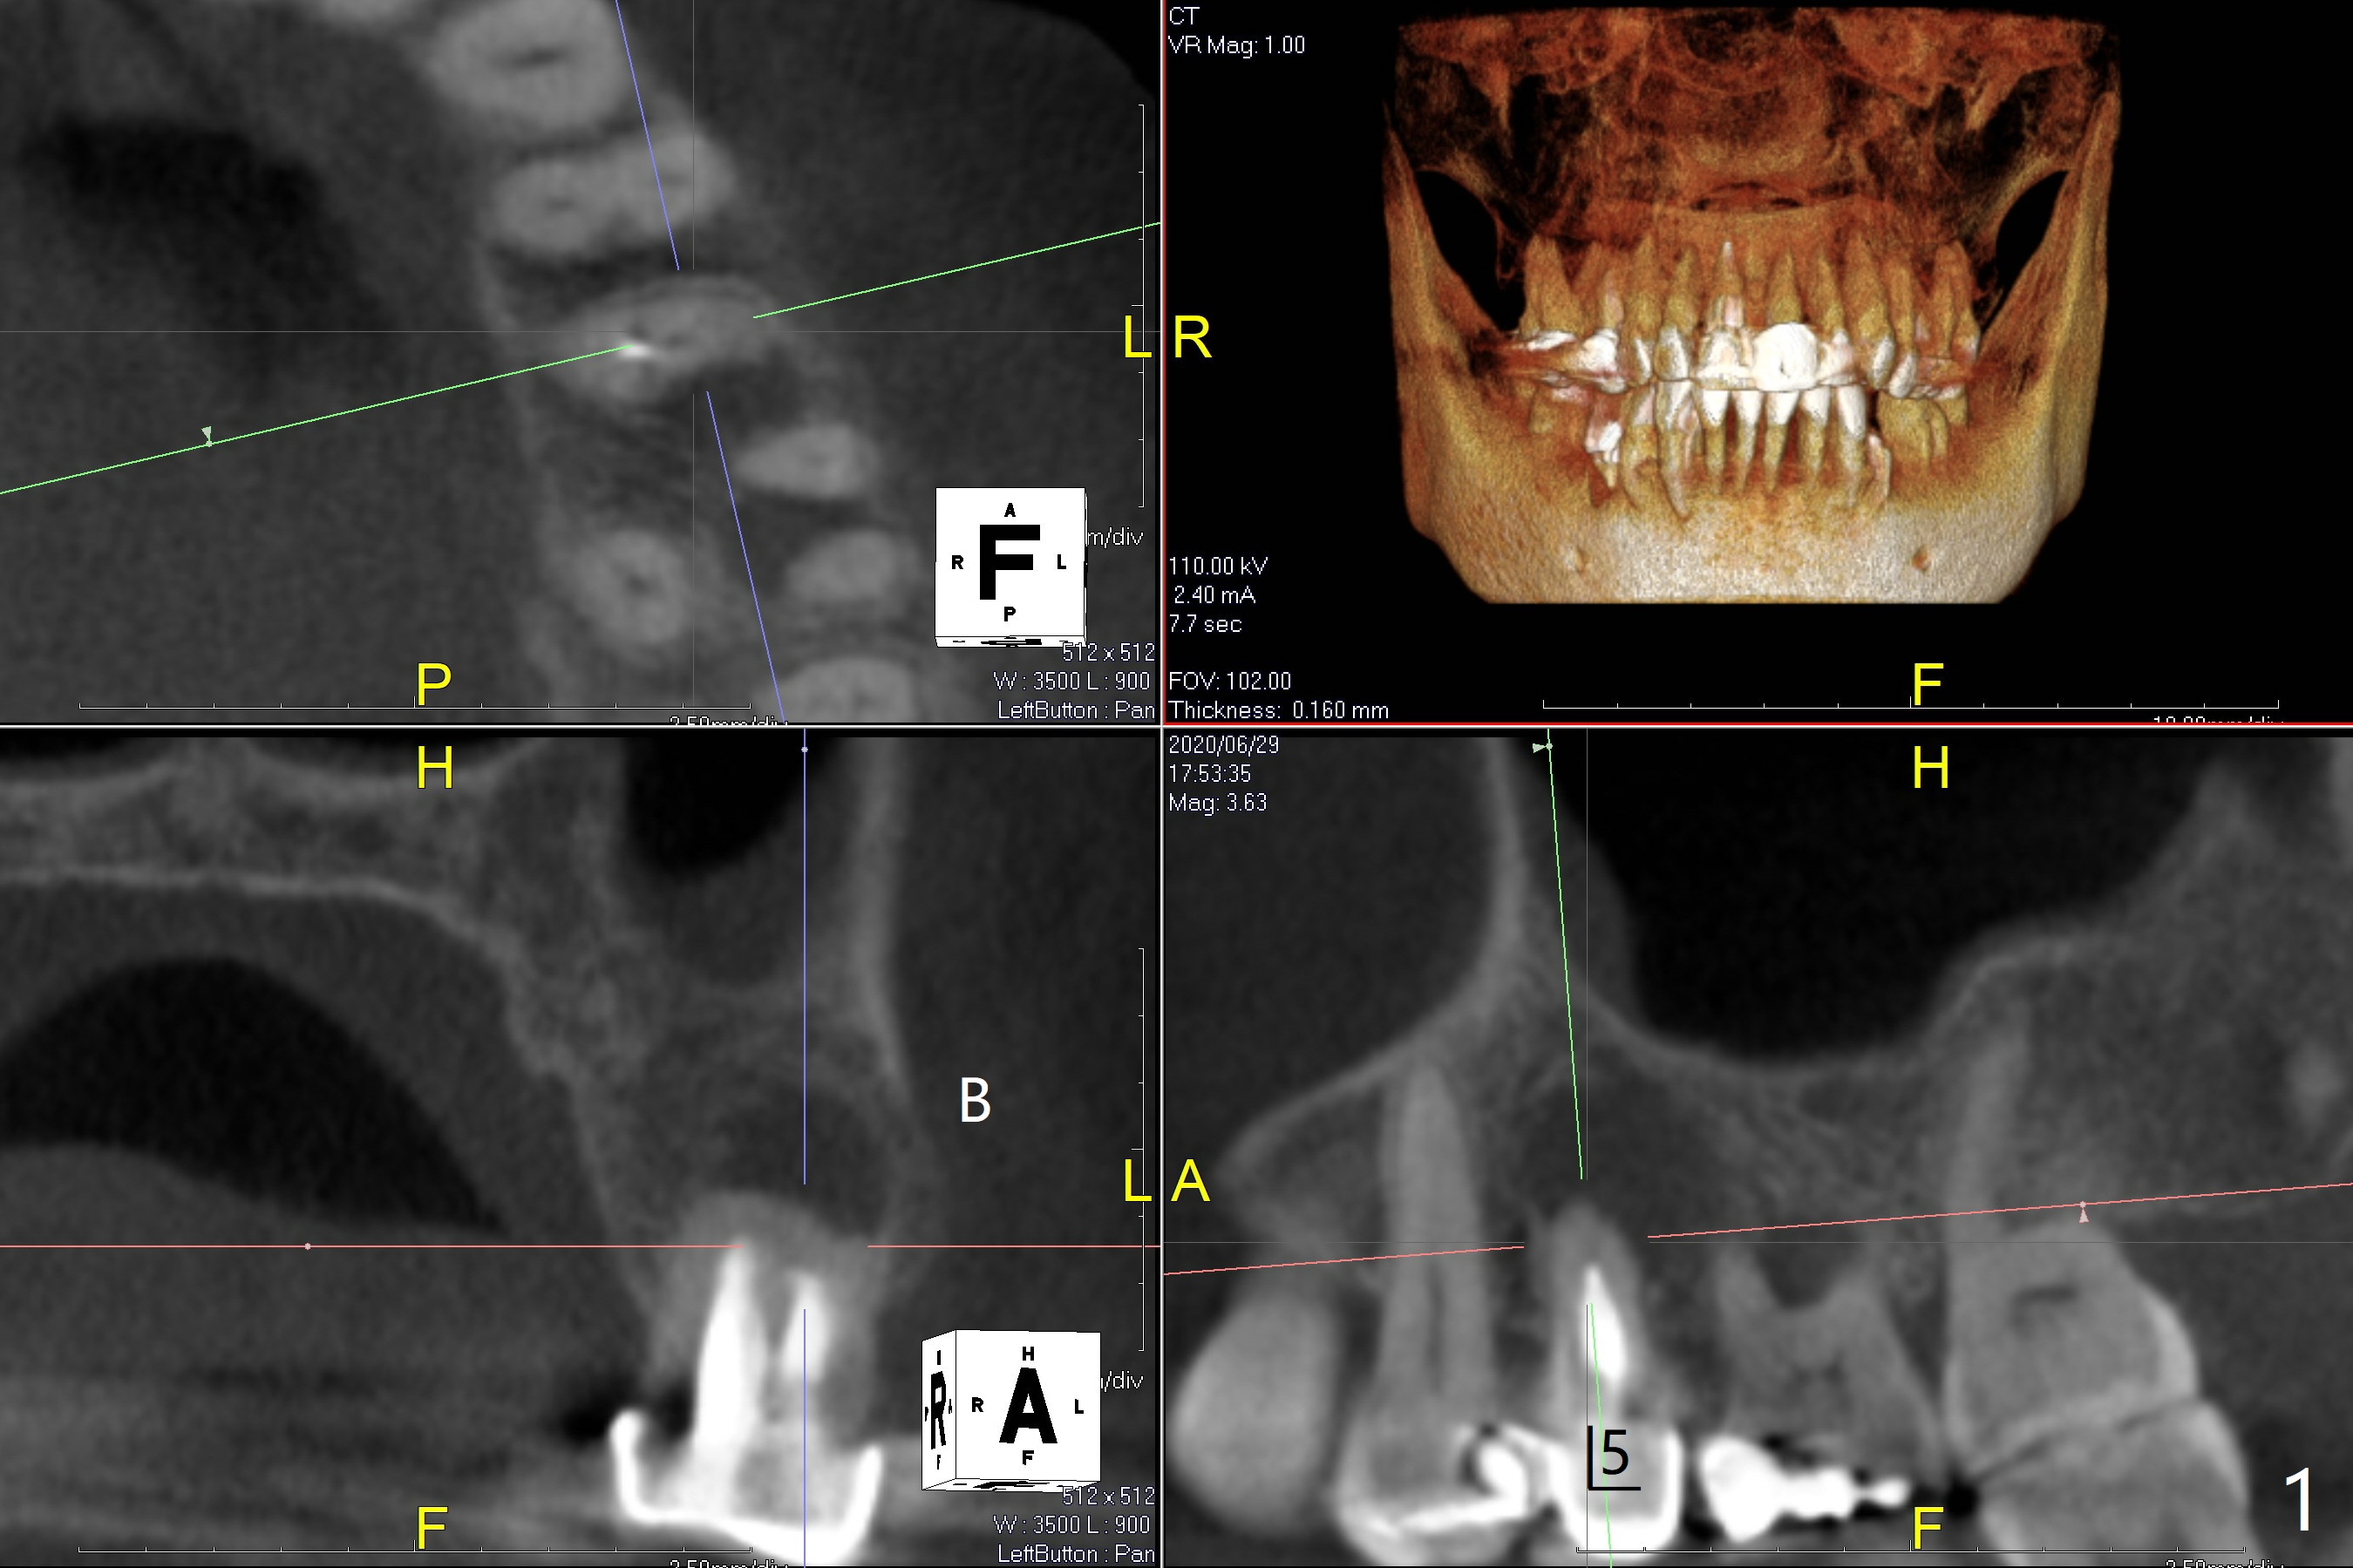

63岁女对肾上腺素和90%以上抗生素过敏,左上5(短根,巨大根尖阴影,图一),左下6(根分叉感染,远中龋齿(图二:*),左下4(牙齿断裂略微龈下:图二,五)似乎很难保留,左下5骨质宽度,高度也允许植牙(图四)。由于左上5需要提升术,可能出现上颌窦感染,Z Pack是否引起过敏反应不确定,拔牙植骨与提升植牙分期做(术前拍摄根尖片)。而下颌一期完成。